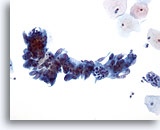

Células endocervicales atípicas (NEOM)

Una capa plana de células glandulares bien organizadas en una disposición de “banco de peces” . Biopsia: Cambios deciduales